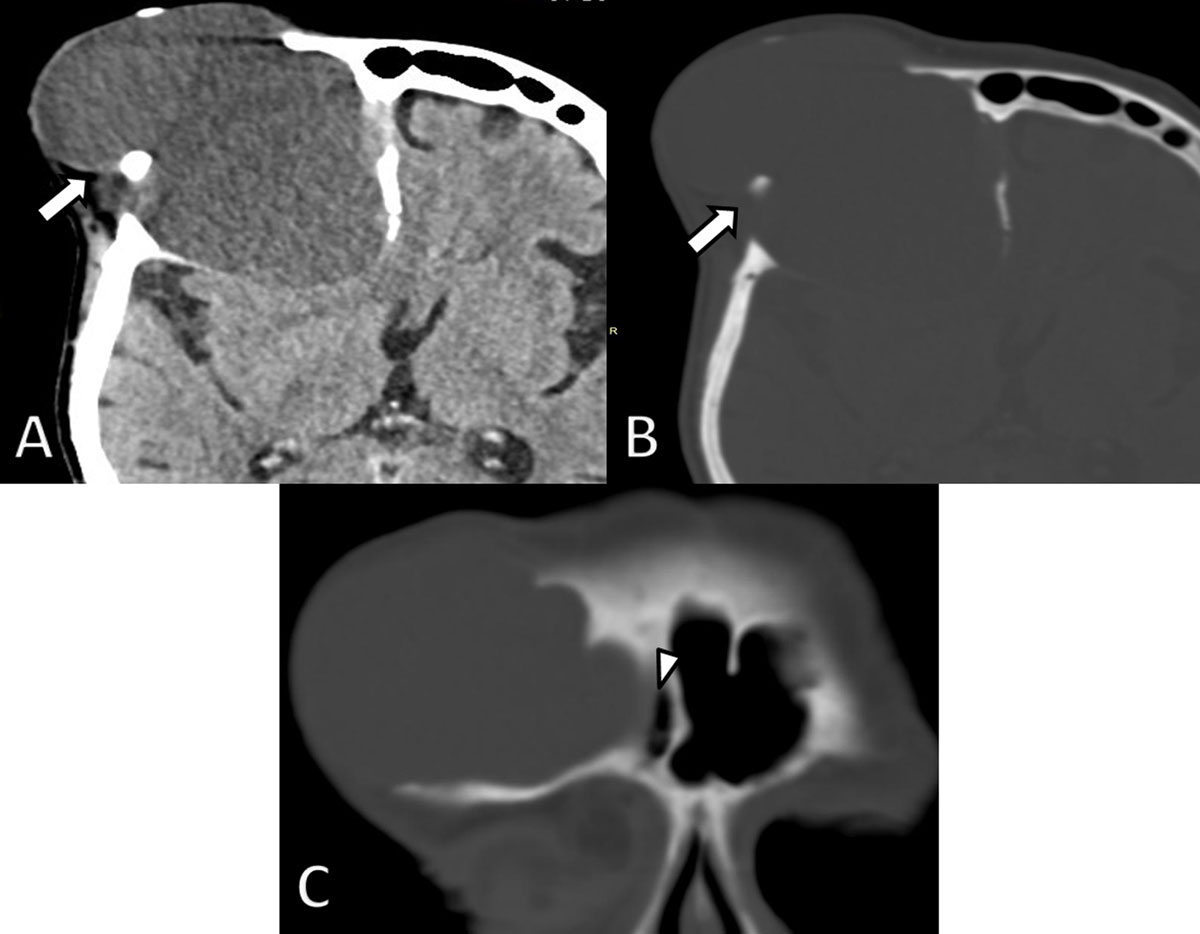

Figure 3

Axial non-enhanced CT images four years later. A. Soft tissue and B. bone window demonstrate considerable growth of the lesion (arrows) and a decrease in density. There is increased osteolytic destruction of the frontal bone and progressive extra-axial extension into the brain with mass effect on the frontal horn of the lateral ventricle. C. Coronal reformatted CT image shows an intimate relationship of the lesion with the right frontal sinus (arrowhead).